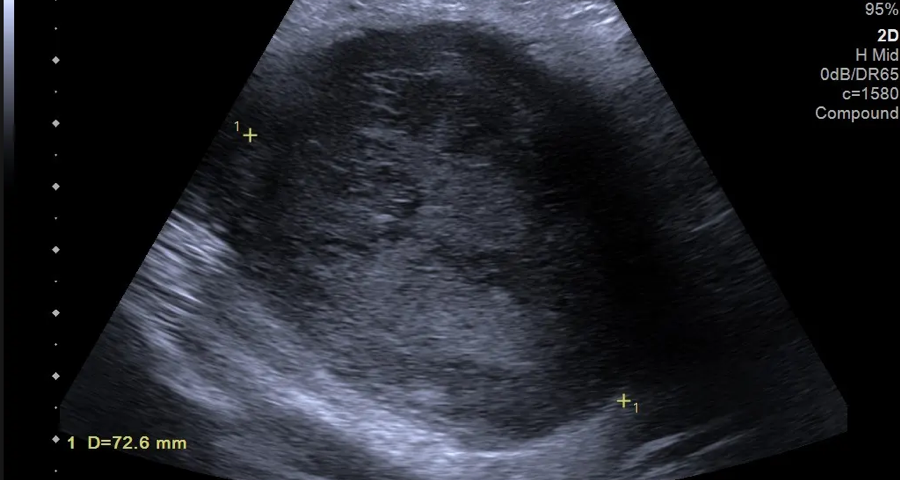

Fig.01.Transverse B-mode extended field of view imaging demonstrates a 7.2 cm well-circumscribed left groin lesion with heterogenous echo texture and increased echogenicity.

Lesion appearances, such as MFS, can be challenging. Ultrasound is a useful adjunct in assessment and differentiation of consistency, vascularity and compressibility. An ultrasound was performed using multi-frequency probes with M-mode and Doppler. The US demonstrated a 7.2cm heterogeneous vascular primary soft tissue tumour rather than an abnormal infiltrated lymph node (Figure 1-3).

Disorganised vascular patterns with abnormal morphology and flow characteristics are recognised as markers of malignancy. The US alone may underestimate deep extension or infiltrative margins, such as in MFS.

Learning Point 2: A comprehensive ultrasound assessment, combined with a focused clinical history and examination at the time of sonographic assessment, is essential in the initial assessment of complex soft tissue lesions. This is supported by the 2024 BMUS assessment of soft tissue lesion guidelines. Suspicious features of malignant soft tissue lesions, such as MFS, including rapid growth, marked intra-lesion vascularity, and a heterogeneous echotexture, were demonstrated in this case. They should prompt further investigation and onward referral.